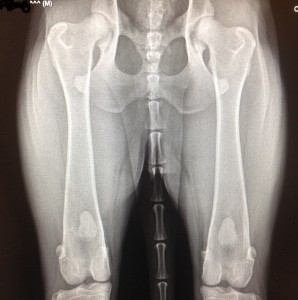

Les deux radiographies montrent des hanches avec une laxité articulaire. Ce sont les premiers signes de dysplasie. On observe souvent ce type de radiographie chez de jeunes chiens dysplasiques. Les têtes fémorales ne sont pas bien enfoncées dans l’articulation. L’espace articulaire est inégal. Les rebords osseux sont encore lisses démontrant encore peu d’ostéoarthrose, qui ne manquera toutefois pas d’arriver avec les années.